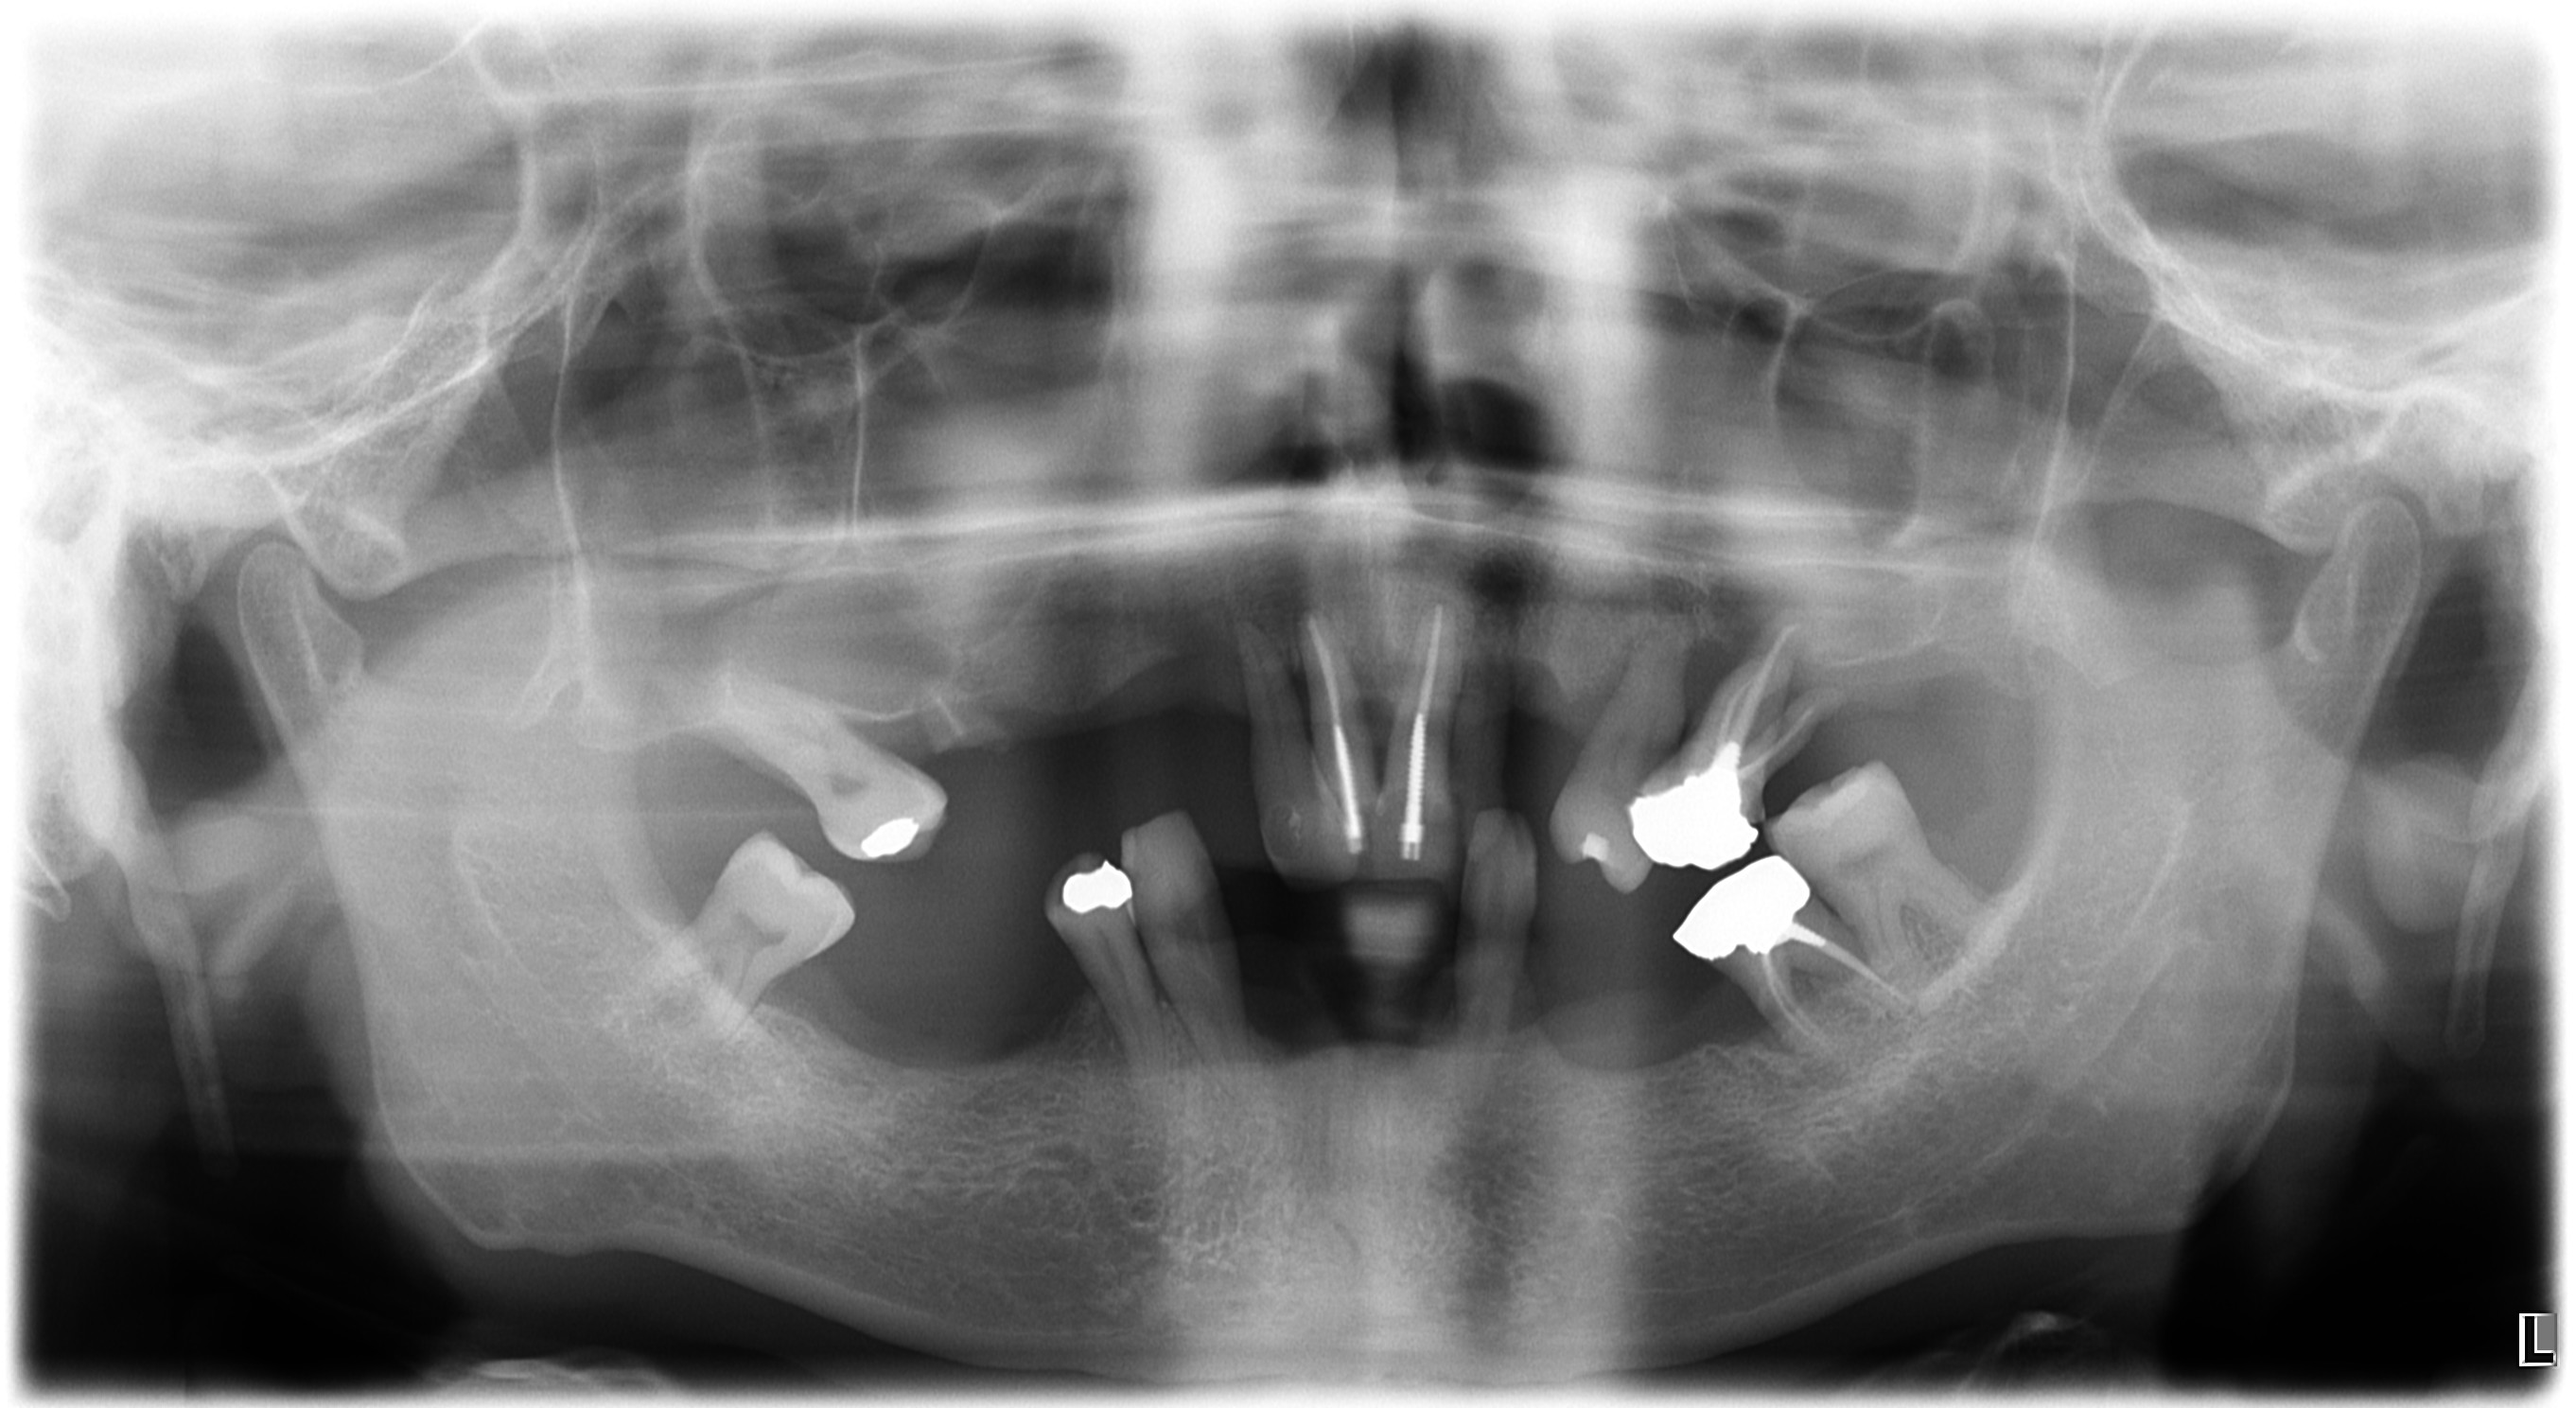

salve volevo un consiglio, mi sono stati proposti soluzioni un intervento per fare 2 impianti zigomatici ma non avendo la masticazione corretta mi sono state proposte 2 protesi mobili da portare x 2 mesi per rimettere a posto la masticazione mascellare e poi procedere a fare gli impianti zigomatici

la seconda proposta sono 4 impianti zigomatici e per correggere la masticazione mascellare con ribasamento della protesi provvisoria grazie a chi mi dara consigli

qui per vedere la TAC https://we.tl/t-fxJnDoj3bV

Bianchetti_Giuseppe_20052019_172649.jpg